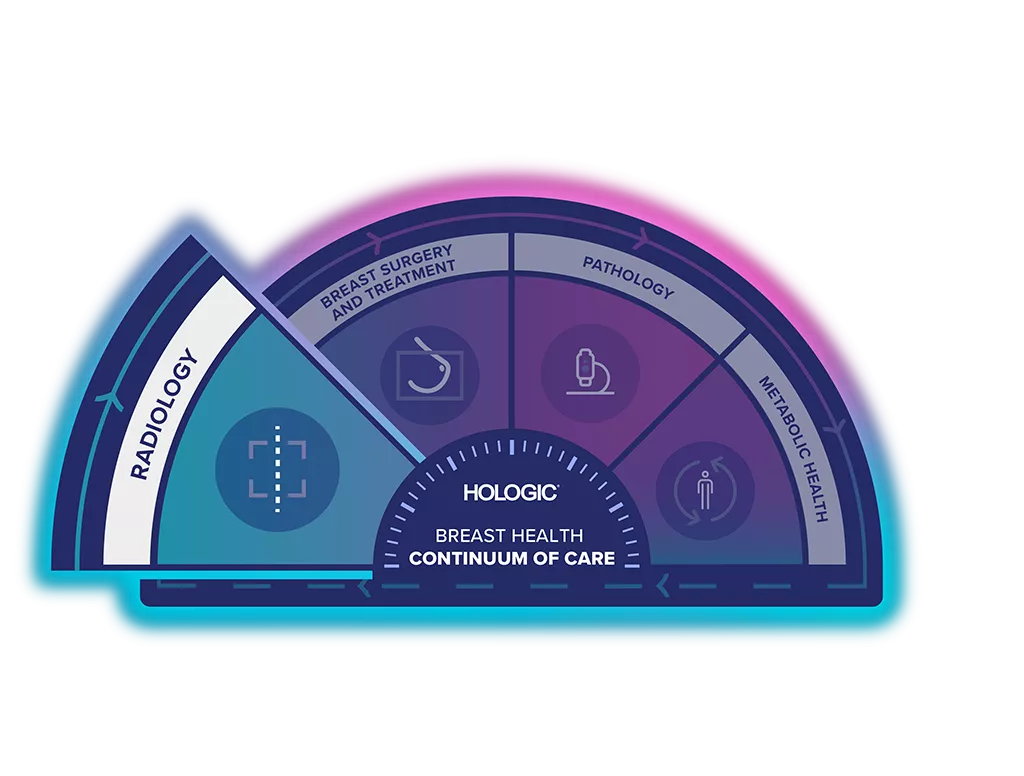

The Breast Health Continuum of Care offers integrated solutions for clinical confidence, workflow efficiency and compassionate patient care. It gives more women, more time in better health.

The Selenia Dimensions Digital Mammography System is part of the Hologic Screening & Diagnosis Solution.

Visit Our Virtual Hospital

Browse our portfolio of Breast Health solutions in 3D. See how you can unlock the advantage of time across the entire Breast Continuum of Care.